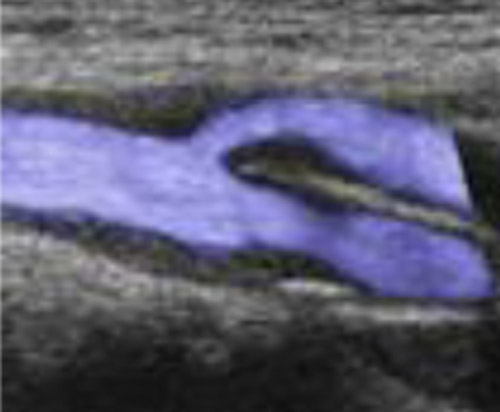

頸部超音波検査

頸動脈に対して行う超音波検査で主に動脈硬化の状態や脳梗塞の病型診断等が可能。